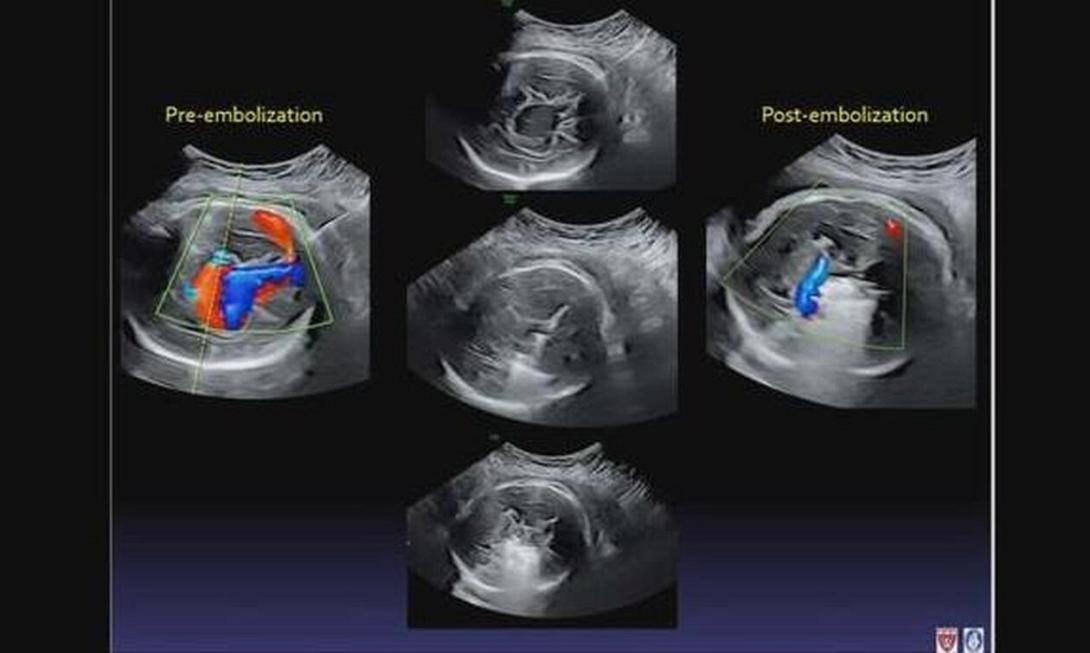

Ο μικρός Ντένβερ μεγάλωνε κανονικά μέσα στη μήτρα της μαμάς του, όταν σε ένα υπερηχογράφημα ρουτίνας, οι γιατροί ανακάλυψαν ότι είχε μια φλέβα δυσπλασίας του Γαληνού, μια σπάνια ανωμαλία των αιμοφόρων αγγείων μέσα στον εγκέφαλο. Πολλά μωρά με αυτή την πάθηση εμφανίζουν καρδιακή ανεπάρκεια ή εγκεφαλική βλάβη και συχνά δεν επιβιώνουν. Στην πραγματικότητα, η καρδιά του Ντένβερ πάλευε και η δυσπλασία γινόταν επικίνδυνα μεγάλη.

Από εκεί, οι γιατροί εισήγαγαν μια βελόνα μέσω του κοιλιακού τοιχώματος, περνώντας προσεκτικά έναν καθετήρα μέσω της βελόνας, έτσι ώστε οι μικροσκοπικές μεταλλικές σπείρες να γεμίσουν τη φλέβα, να επιβραδύνουν τη ροή του αίματος και να μειώσουν την πίεση.

Το μωρό έδειξε σημάδια βελτίωσης αμέσως, με τις σαρώσεις να δείχνουν μειωμένη αρτηριακή πίεση σε βασικές περιοχές.